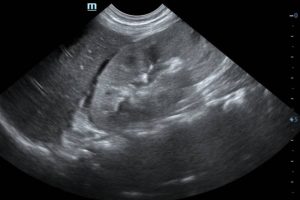

Фото МРТ надпочечников

Андростерому можно диагностировать, основываясь на клинических проявлениях, а также на результатах лабораторных и инструментальных исследований. Эти методы не только подтверждают предварительный диагноз, но и помогают отличить заболевание от других патологий, которые также могут вызывать вирилизацию. Для этого применяются следующие методы:

- МРТ. Данный метод сканирования позволяет определить точные размеры и расположение опухоли.

- РКТ. Этот способ визуализации помогает четко увидеть андростерому, чаще всего опухоли обнаруживаются в одном из надпочечников.

- Ангиография надпочечников. Эта диагностическая процедура исследует состояние кровеносных сосудов, которые питают почки, и помогает установить продолжительность патологического процесса.